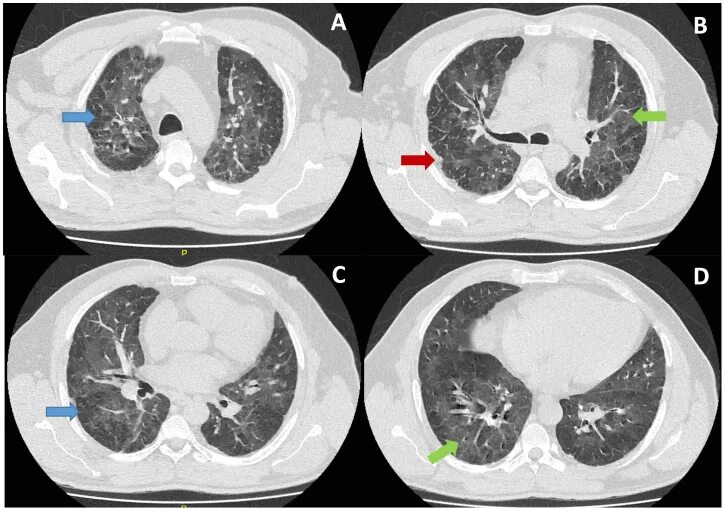

Бронхиолит причины